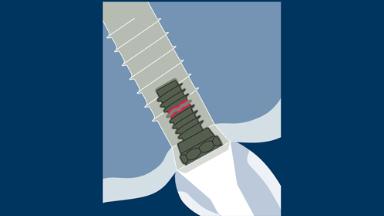

A terapia com implantes provou ser uma modalidade de tratamento bem-sucedida, aplicável em uma ampla gama de indicações clínicas para substituição dentária. Mesmo assim, as complicações ocorrem, e há evidências claras de que as complicações protéticas ocorrem em maior proporção com implantes dentários do que com dentes naturais. Geralmente chamados de “complicações estruturais”, é importante entender porque elas ocorrem e qual a melhor forma de lidar com elas. Este módulo classificará as complicações estruturais do implante associadas às próteses fixas como base para elucidar suas várias causas, melhor prevenção e manejo.